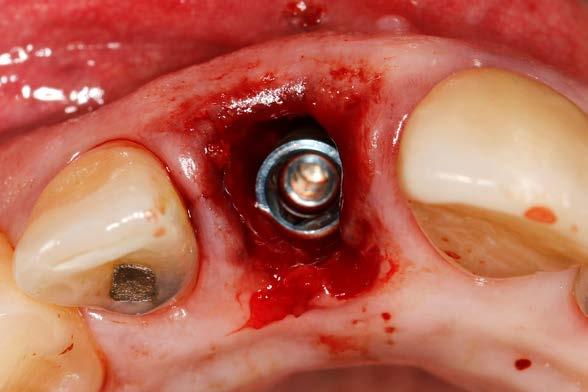

Presentamos el caso de un paciente varón de 47 años, que acude a la consulta dental por presentar dolor, movilidad y fístula en la pieza dental 11. Este caso, fruto de un traumatismo previo, tuvo que ser endodonciado y posteriormente realizada sobre el mismo una apiceptomía, para abordar un quiste apical residual que no terminaba de evolucionar de forma favorable. El trabajado de rehabilitación posterior se llevó a cabo con una reconstrucción con poste y una carilla cerámica. Tras varios años, el diente ha comenzado de nuevo con los síntomas anteriormente descritos por lo que se sospecha la presencia de una fractura radicular. La

radiografía panorámica inicial para el diagnóstico nos aporta una imagen radiolucida entorno al ápice del diente en posición 11 ( Figura 1 ). Para conocer mejor el alcance de la lesión y las opciones terapéuticas de las que disponemos se lleva a cabo un cone-beam en el que se puede objetivar de forma precisa el defecto apical al diente. Este defecto es circunferencial y está dejando una reabsorción casi completa de la tabla ósea vestibular y parcial de la palatina, con un grosor de 1.9 mm, como vemos en el corte seccional (Figura 2). Si observamos la medida total en la zona media del incisivo dentral, necesitamos cubrir una anchura aproximada de 8 mm por lo que el implante que coloquemos irremediablemente dejará un gap, que según los protocolos quedará en vestibular. Utilizando una plataforma estándar de 4.1 mm el gap a rellenar será prácticamente de 4 mm según las medidas que nos

nos permita la carga inmediata posterior. En este caso 11.5 mm (Figura 3 y 4).Una vez diagnosticado el caso de forma correcta con las imágenes del cone-beam iniciamos la fase quirúrgica. Realizamos la exodoncia del diente 11 con el menor trauma

Figura 3. Diámetro del alveolo tras la exodoncia del diente 11.

5 y 6. Alveolo tras la extracción atraumática del diente en posición 11, conservándose al máximo los tejidos duros y blandos para la colocación posterior del implante.

posible sobre los tejidos blandos y sobre el hueso remanente (Figura 5 y 6). Procedemos posteriormente a realizar una secuencia de fresado adaptada al lecho postextracción, alargando el alveolo con las fresas apicalmente y hacia palatino, donde se producirá el anclaje del implante. Con el lecho preparado colocamos el implante, quedándonos en vestibular el gap esperado de aproximadamente 4 mm como podemos ver en la

Figura 7. La utilización de un implante de longitud mayor y la inclinación hacia palatino nos permite lograr la estabilidad primaria necesaria para poder llevar a cabo una carga inmediata del implante. Una vez finalizada la inserción colocamos el transepitelial unitario para trabajar sobre el mismo generando la prótesis provisional de carga inmediata. Esta pieza intermedia (implante-prótesis) nos permite el uso de una interfase,

Figura 7. Imagen tras la colocación del implante ligeramente palatinizado con el gap situado en vestibular.

Figura 8. Imagen del implante colocado en el alveolo con el transepitelial unitario para llevar a cabo la carga inmediata.